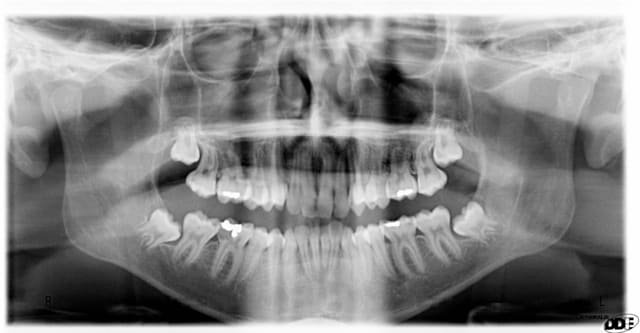

quel est l'age du patient?

est-elle symptomatique? perso je pense que non

est-elle sondable en bouche? perso je pense que non

Changement en 4 ans de 17ans à 21 ans?

Ton panorex céramik est extraordinaire, j'aurais mis le titre: potentielle d'éruption dans la branche montante

Excellent exemple d'un cas où il fallait agir...

J'aurais enlever dans la 1er pano, 100%, aucune hésitation.

Dans la 2e pano, j'adresse et le pauvre patient aura des emmerdes.

bonjour,tu dois parler des huit du haut sans doute ???

Dans la 1er pano, j'enlève toutes les 8

Dans la 2e pano, je touche pas.

Note: il y a une obturation sur la 18 ????????

la 18 et 28 sont en occlusion avec le tiers distal des 37-47..

Pas grave, ça pousse la bouffe au distal des 37 et 47, et tu as là des 48 et 38 bien mal placées.

Enlève déjà les 18 et 28.

Vu le niveau d'hygiène du patient quand on compare le nombre d'obturations entre 17 et 21 ans, la malposition...on peut probablement prédire une complication ifectieuse sur 38-48 dans les années

Concernant les 18-28 sont simples à enlever, en une séance et le tour est joué.

Concernant les 38-48 il n'y a en principe pas de difficulté opératoire mais à présent il ne faudra les enlever que si y'a des symptômes infectieux récurrents.

pas d'accord pour la 38 communication en bouche indication formelle d'extraire, ne pas attende infection à 50 ans et perdre la 37 du même coup.

Et la 48, ne pas attendre non plus, car ça sera la même chose.

Illico, exo des 4 dds.

38 et 48 à extraire ou alors tu vas jouer à la roulette russe pour le maintien des 7.

Demande un dentascan pour la 48 pour programmer une éventuelle coronectomie.